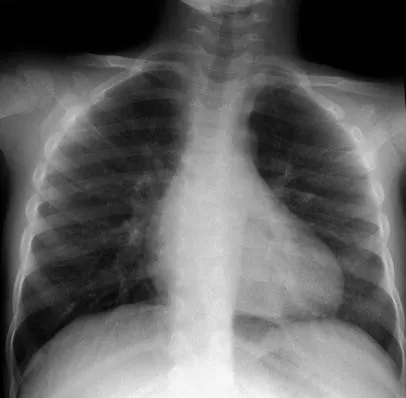

Diagnosis: Primarily clinical. Chest X-ray is not routinely recommended but may show hyperinflation, peribronchial thickening, and atelectasis.